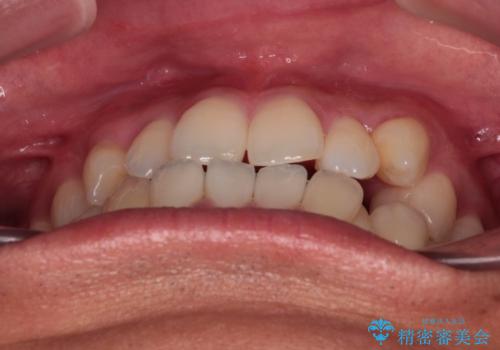

- 上下前歯部のデコボコを主訴として来院された患者様です。

上顎の歯列弓が下顎に対して狭いため、臼歯のかみ合わせがが咬頭対咬頭の状態です。

歯列弓の拡大により約1年で矯正治療を終えることができました。

正中も合わせることができ、非常にきれいに仕上がりました。